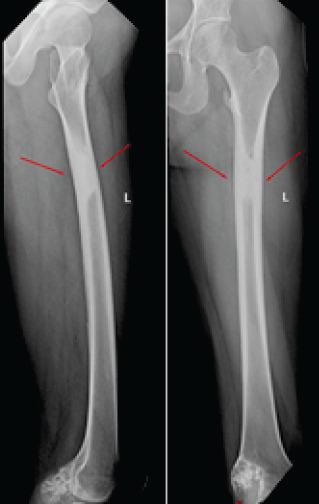

Melorheostosis is a rare condition affecting the bones and has only been occasionally reported. We herein report a case of melorheostosis affecting left femur and tibia which was diagnosed based on clinical and radiological features and managed with bisphosphonates.

A 28-year-old female patient presented with complaints of pain over left knee and thigh for the past 3 months. To evaluate the cause of pain X-ray and magnetic resonance imaging were done, which revealed characteristic candle dripping wax appearance suggestive of melorheostosis. After arriving at the diagnosis patient was started on nonsteroidal anti-inflammatory drugs and pamidronate which provided symptomatic betterment patient has now been followed up for past 1 year and is symptom free.

骨蜡油样骨病是一种影响骨骼的罕见病症,仅有零星报道。我们在此报告一例累及左股骨和胫骨的骨蜡油样骨病病例,该病例根据临床和放射学特征得以诊断,并采用双膦酸盐进行治疗。

一名28岁女性患者,过去3个月来一直诉说左膝和大腿疼痛。为评估疼痛原因,进行了X线和磁共振成像检查,结果显示出具有特征性的烛泪样外观,提示为骨蜡油样骨病。确诊后,患者开始服用非甾体类抗炎药和帕米膦酸盐,症状有所改善。患者现已接受了1年的随访,目前无症状。